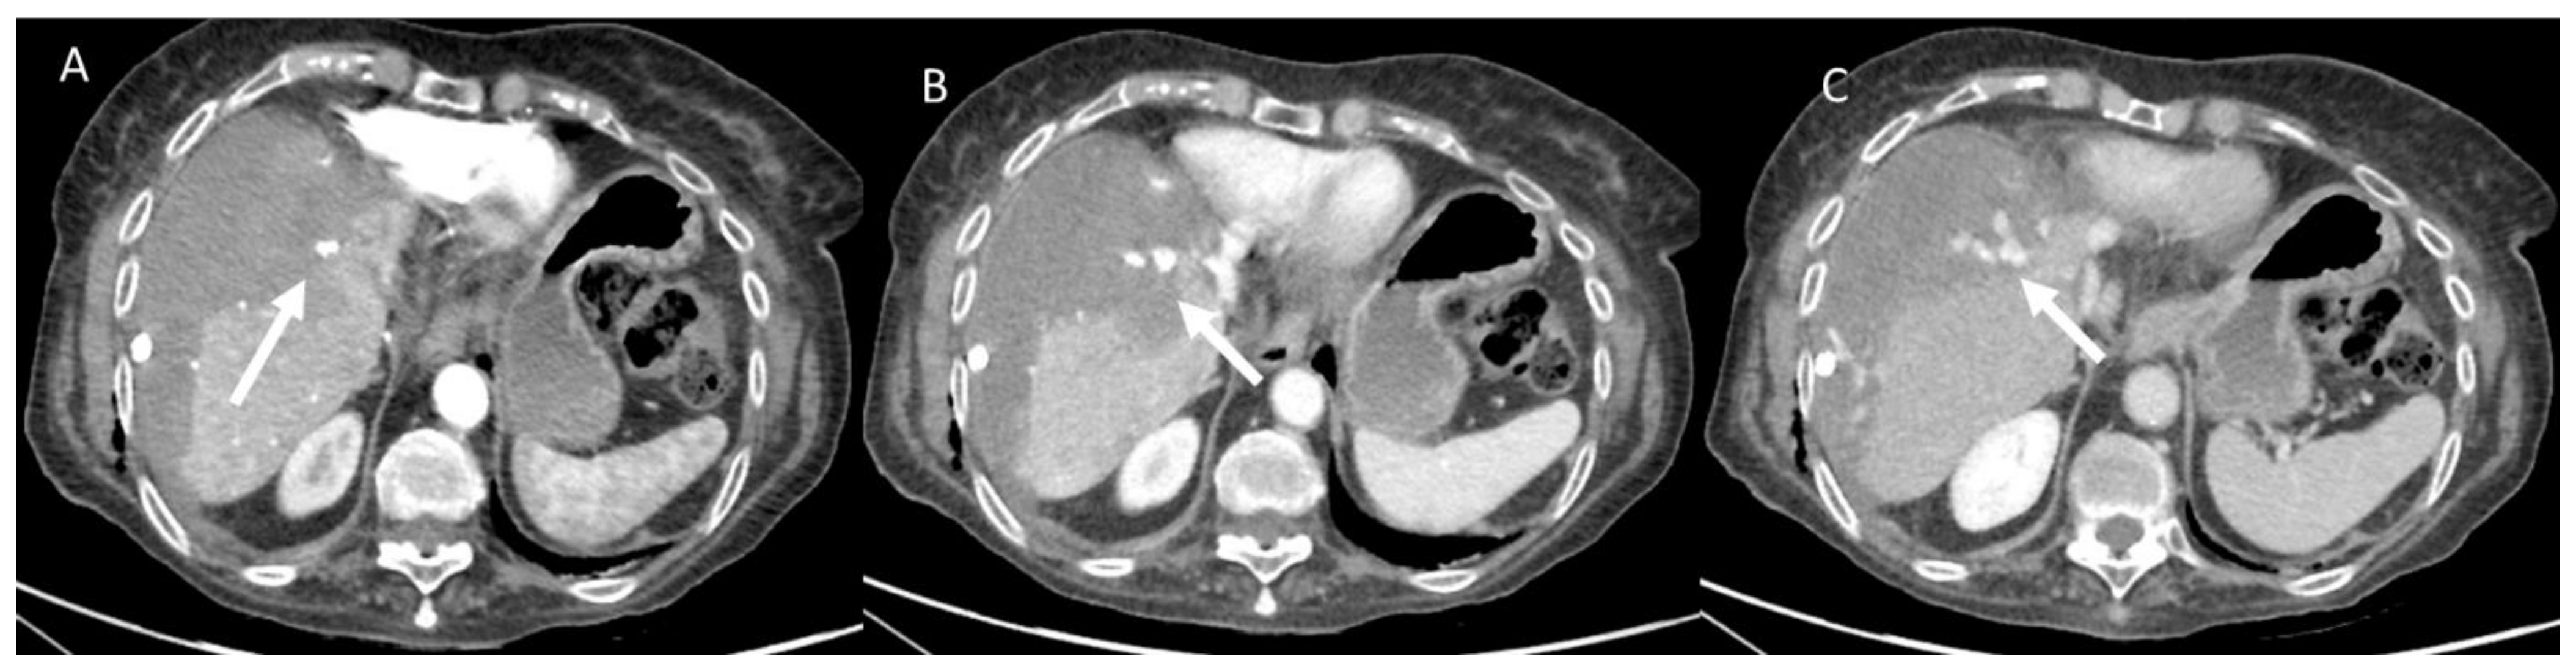

- Granata, V.; Grassi, R.; Fusco, R.; Belli, A.; Cutolo, C.; Pradella, S.; Grazzini, G.; La Porta, M.; Brunese, M.C.; De Muzio, F.; et al. Diagnostic evaluation and ablation treatments assessment in hepatocellular carcinoma. Infect. Agents Cancer 2021, 16, 53. [Google Scholar] [CrossRef] [PubMed]

- Granata, V.; Grassi, R.; Fusco, R.; Setola, S.; Belli, A.; Piccirillo, M.; Pradella, S.; Giordano, M.; Cappabianca, S.; Brunese, L.; et al. Abbreviated MRI Protocol for the Assessment of Ablated Area in HCC Patients. Int. J. Environ. Res. Public Health 2021, 18, 3598. [Google Scholar] [CrossRef]